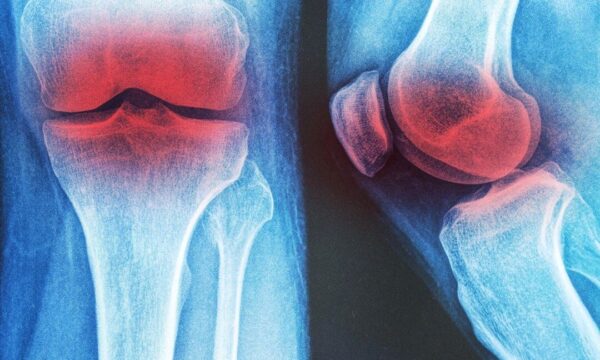

2025/09/22

Mary West

膝の変形性関節症に効く 3つの非薬物療法

2025/04/26

Ellen Wan

変形性関節症が引き起こすリスクとは? 慢性疾患の連鎖を防ぐ予防法